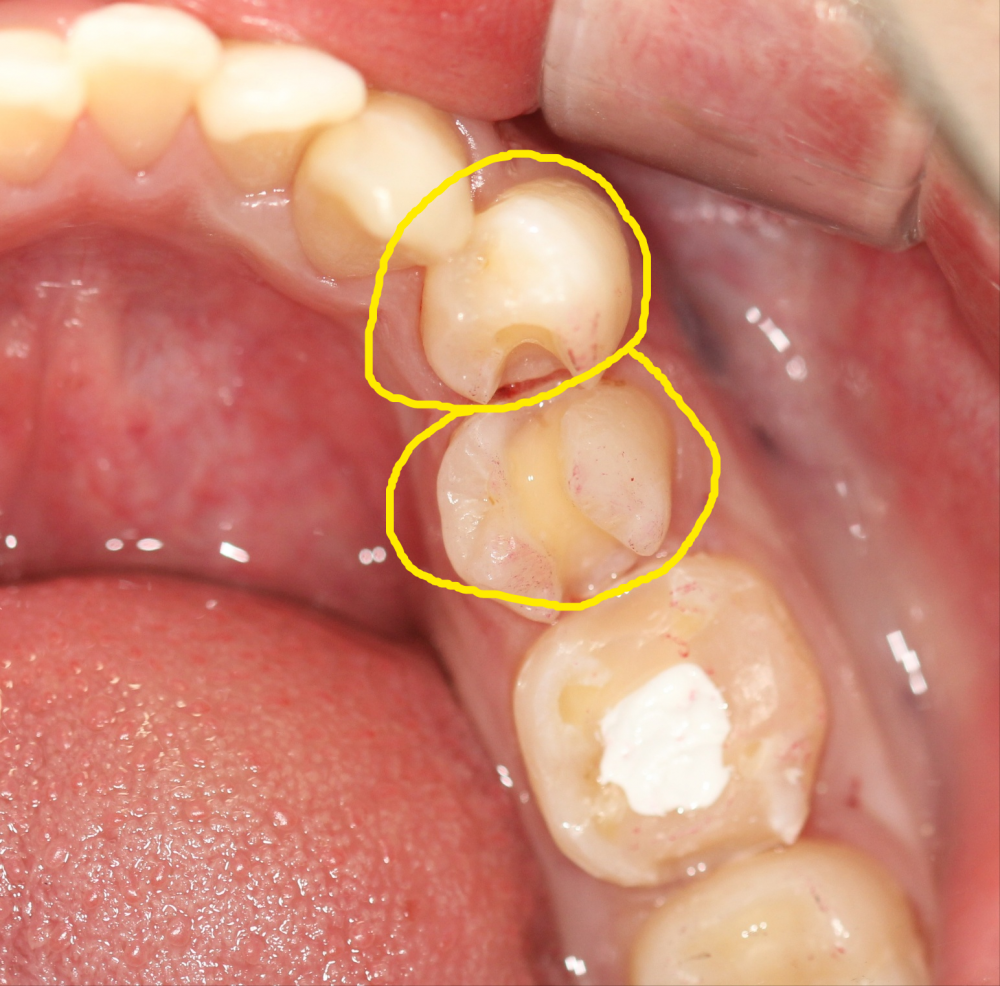

퀴즈! 이맥스 인레이치료한 치아를 찾아주세요

힌트 : 2개

답: 작은어금니 2개